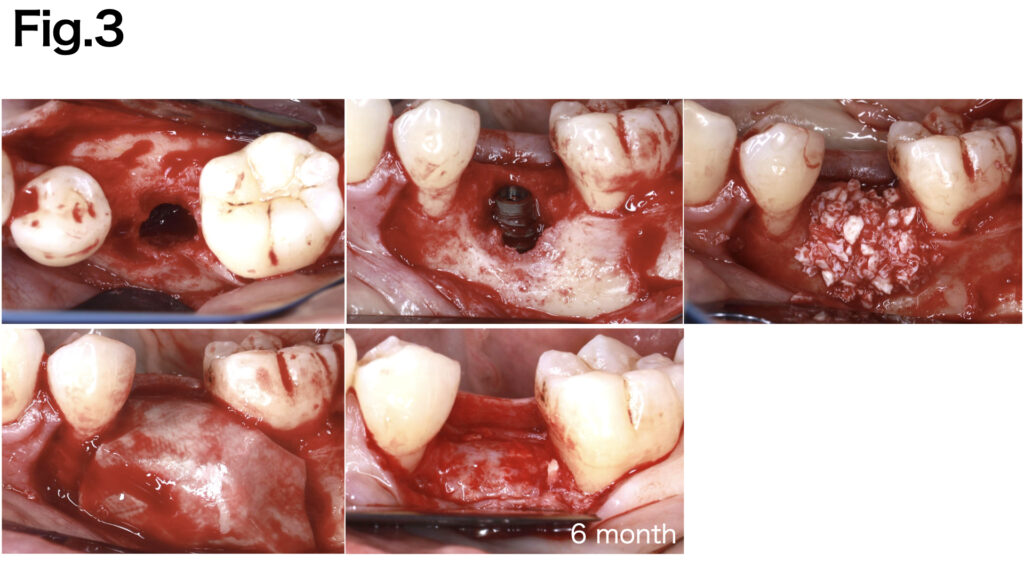

CASE 4 (Type Ⅲ)

Due to the extensive width of the bone defect and the absence of basal bone, stabilizing the grafted bone was challenging. Fixation pins were applied to both the buccal and lingual aspects to achieve secure fixation of the e-PTFE membrane (NeoGen®). After six months of healing, sufficient bone regeneration was achieved.

CASE 5 (Type Ⅳ)

A severely atrophic horizontal bone defect was observed. Fixation pins were applied to both the buccal and lingual aspects to achieve secure fixation of the e-PTFE membrane (NeoGen®︎). After six months of healing, adequate bone regeneration was achieved.